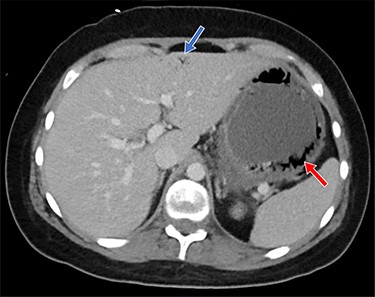

Clinical and laboratory examination revealed slightly elevated C-reactive protein (CRP, 71.1 mg/l [normal range < 10 mg/l]) and potassium (5.1 mmol/l [normal range 3.6–4.8 mmol/l]) levels. The cyclosporine dosage was reduced, causing initial improvement of symptoms. Because of recurrent hyperpotassemia of 5.5 mmol/l 12 days post-transplantation, the patient received 15 mg of SPS orally. The same day, the patient complained of progressive abdominal pain. His body temperature was 38.5°C, heart rate at 91 beats per minute, blood pressure at 126/80 mmHg, and peripheral oxygen saturation levels at 95% breathing ambient air. The abdomen was bloated without signs of peritonitis. White blood cell count was 1.03 × 109/l (normal range 3.50–10.00 × 109/l) and neutrophils 0.18 × 109/l (normal range 1.300–6.700 × 109/l). The CRP levels rose to 109 mg/l. Given the elevated CRP levels, combined with progressive abdominal discomfort and fever, a thoracoabdominal computed tomography (CT) scan was obtained. CT scan showed a thickened gastric wall with gastric pneumatosis (GP) accompanied by air in the hepatic portal vein system (Fig. 1).

Shown is air in the gastric wall (red arrow) and air in the hepatic portal venous system (blue arrow)